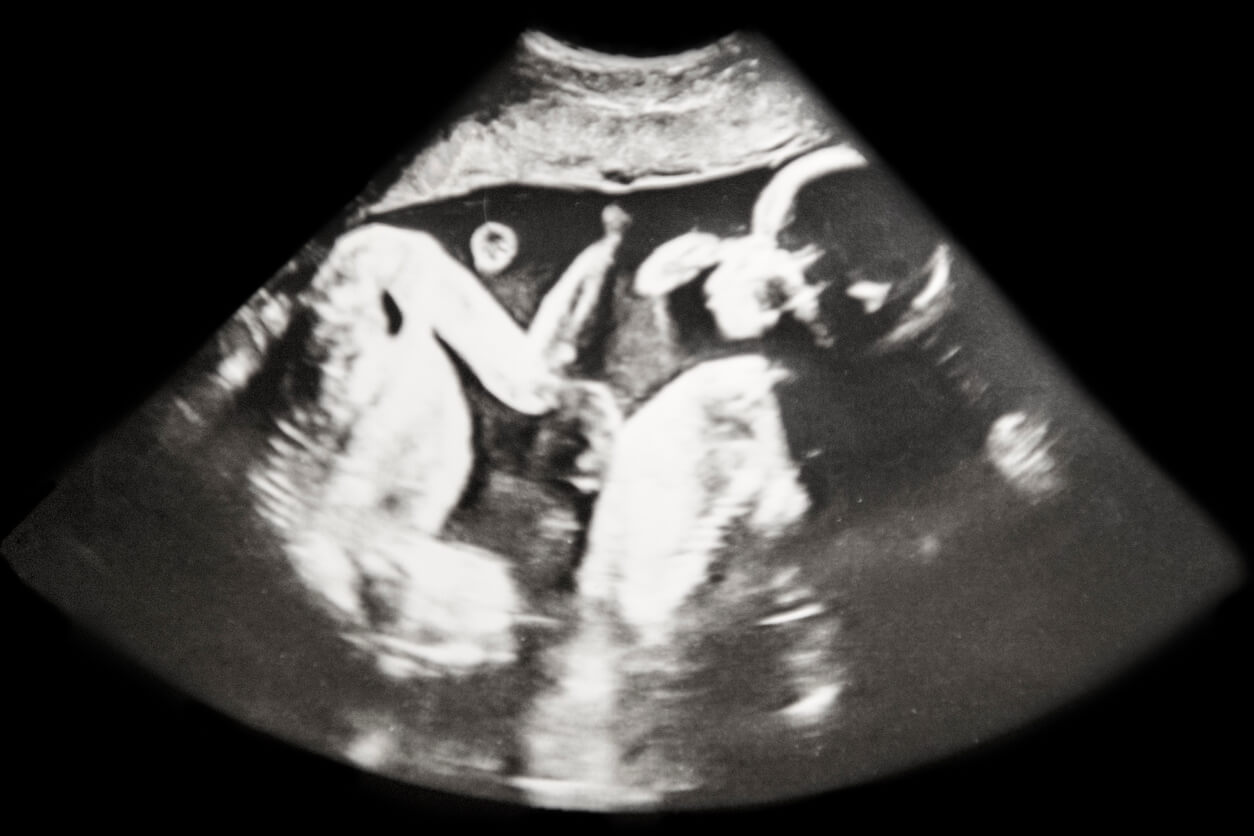

Questa condizione è più comune nelle gravidanze multiple, specialmente nella prima gravidanza. Di solito si verifica sul lato sinistro e la sua intensità è variabile: dalla lieve instabilità articolare alla completa lussazione dell’anca.